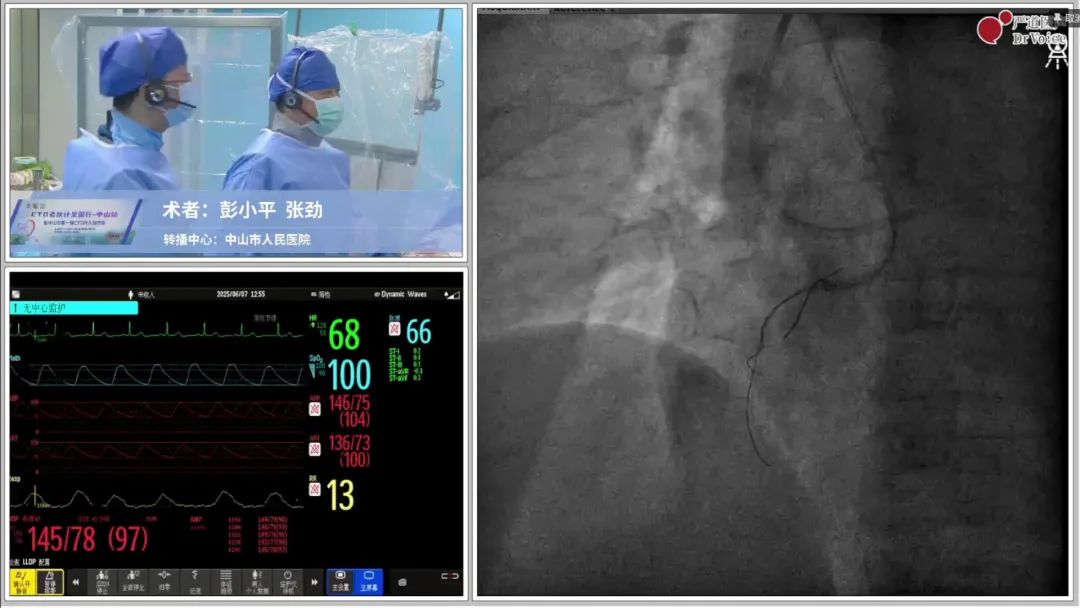

此外,后续登场的术者更是将实战推向了高潮,来自南昌大学第一附属医院彭小平教授、首都医科大学附属北京安贞医院张宇晨教授、湖南省人民医院潘宏伟教授、中南大学湘雅三医院曹宇教授、山东第二医科大学附属医院李敬田教授、温州医科大学附属第二医院官学强教授、台山市人民医院陈炎教授、深圳市人民医院尹达教授、中山市人民医院张励庭教授相继演示了多台难度与高度并存的CTO PCI手术。

从通过IVUS指导精准穿刺纤维帽到联合双导丝锚定技术,再到逆向微导管对吻技术突破前降支齐头闭塞、心外膜侧支逆向开通左回旋支CTO,演绎高风险路径的精细操控、腔内影像优化支架植入,实现左主干-前降支血运重建,每台手术不仅展现了我国冠脉介入技术的百花齐放,更以实战印证了“老伙计”们攻坚复杂病变的智慧与担当。